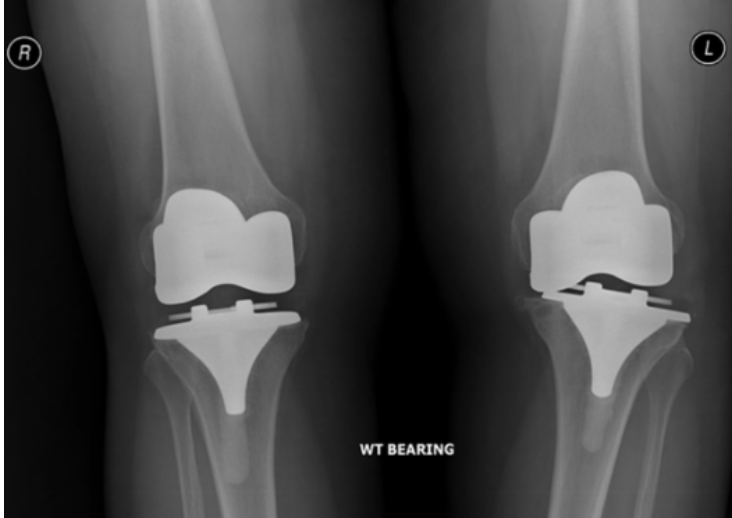

Knee Conditions GET IN TOUCH Knee Arthritis Meniscal Tears ACL Tears Knee Instability The Painful Or Failing Knee Replacement Knee Arthritis Learn MOre Meniscal Tears Learn MOre ACL Tears Learn MOre Knee Instability Learn MOre The Painful Or Failing Knee Replacement Learn MOre KNEE SURGERY OUR SERVICES If joint pain or injury is affecting your daily life, Dr Paterson is here to support your recovery with individualised, evidence-based care. Knee Arthritis Learn MOre Meniscal Tears Learn MOre ACL Tears Learn MOre Knee Instability Learn MOre The Painful Or Failing Knee Replacement Learn MOre OTHER TREATMENT OPTIONS